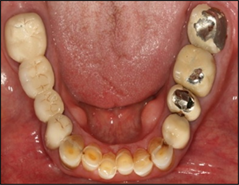

The present study was carried out in the department of periodontics and community dental sciences (PCS), college of dentistry, king Khalid university, Saudi Arabia for a period of 6 months from January 2016 to June 2017. A total of 292 patients (152 males) and (140 females) were evaluated for the effect of the dental restorations type of marginal bone loss among some patients being treated for chronic periodontitis. They were divided according to dental reconstructions into three groups, group I included 102 patients (52 males and 50 females) without dental reconstructions (control group), group II included 95 patients (50 males and 45 females) patients received amalgam class II fillings and group III included 95 patients (50 males and 45 females) received fixed bridge denture (FPDs) (Figure 1 and Figure 2).

Figure 2. Clinical examination of patient with fixed partial.